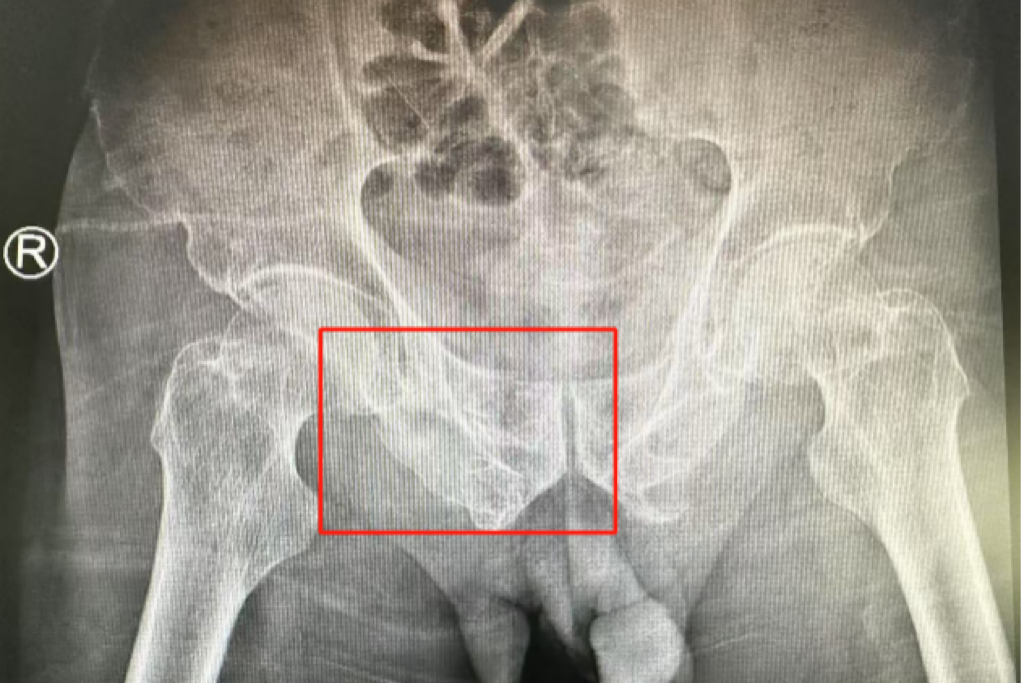

術(shù)前影像學(xué)顯示,患者的左側(cè)骶骨骨折,右側(cè)恥骨骨折、髂骨骨折,骨盆骨折分型為C型,老年脆性骨盆骨折分型為IV型,是極度不穩(wěn)定型的前環(huán)骨折和雙側(cè)后環(huán)骨折。所幸沒(méi)有明顯的骨盆出血或內(nèi)臟損傷的表現(xiàn)。

術(shù)后第二天,醫(yī)生團(tuán)隊(duì)復(fù)查X片顯示螺釘植入位置非常滿意,骨折基本達(dá)到穩(wěn)定復(fù)位,同時(shí),復(fù)查的全血細(xì)胞計(jì)數(shù)中,血紅蛋白指數(shù)為102g/L。術(shù)后第三天,在智能骨科病房護(hù)理團(tuán)隊(duì)及康復(fù)師的指導(dǎo)和護(hù)理下,王大爺可以坐立在床上。術(shù)后第四天,王大爺迎來(lái)了出院日,“得虧有了這么先進(jìn)的醫(yī)療技術(shù),讓我還能下地行走,謝謝你們!”

螺釘植入位置非常滿意

王大爺身體恢復(fù)良好